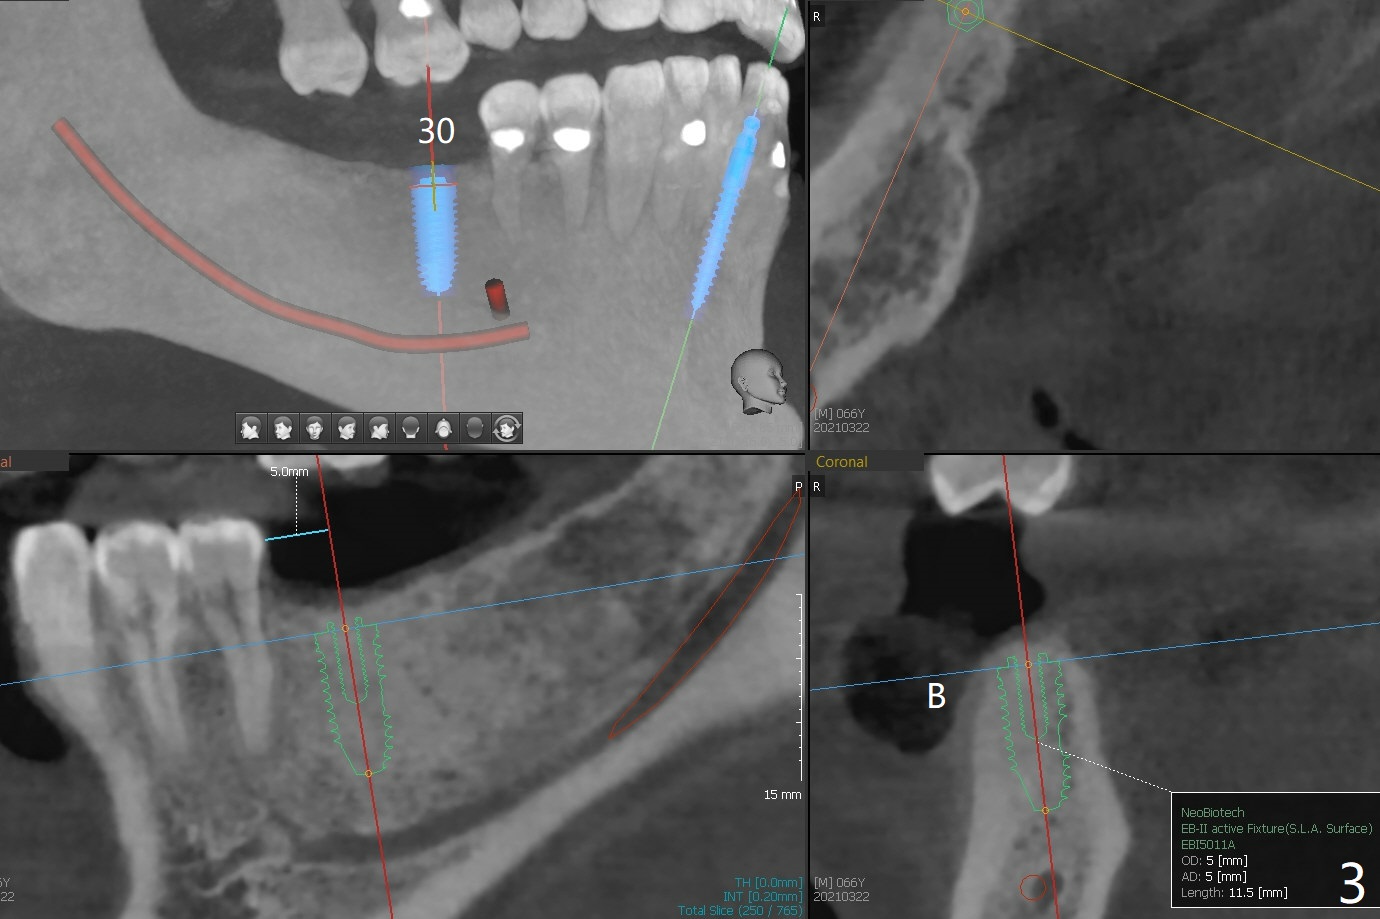

A 66-year-old man requests implant placement at #24, 30 and 31 (Fig.1). Bone loss at #19 and 24 lingual (Fig.2) suggests bruxism. The implant at #24 will be as buccal and mesial (to close the diastema between 24 and 25 (Fig.1 *)) as possible (Fig.2). The vertical space for restoration of 30 and 31 implants (Fig.3,4) is limited; the cusps of the opposing teeth may need to be trimmed.